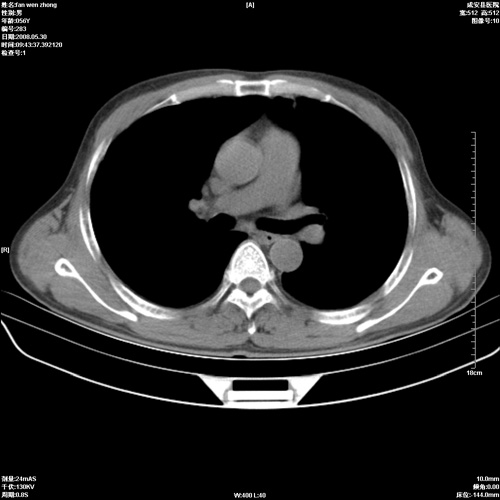

病人 男 56岁 一周前高热,体温达39-40度,经抗炎治疗后,体温渐降,达37,5-38度,轻微咳嗽,胸部不适 查白细胞为1.3万 行ct检查,请分析。

双肺内可见多发结节状病灶,并见小空洞,病人高热,白血球增高,应该是典型的迁徙性肺脓肿(多为金黄色葡萄球菌感染)。查一下口腔等其它部位有无感染灶。

双肺内可见多发结节状病灶,并见小空洞,病人高热,白血球增高,应该是典型的迁徙性肺脓肿(多为金黄色葡萄球菌感染)。建议治疗后复查.